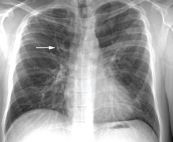

Hình ảnh áp xe phổi phải có mức nước mức hơi trên phim chụp x quang phổi thẳng được thể hiện như thế nào? Mời các bạn tham khảo bài viết dưới đây để hiểu rõ hơn nhé!